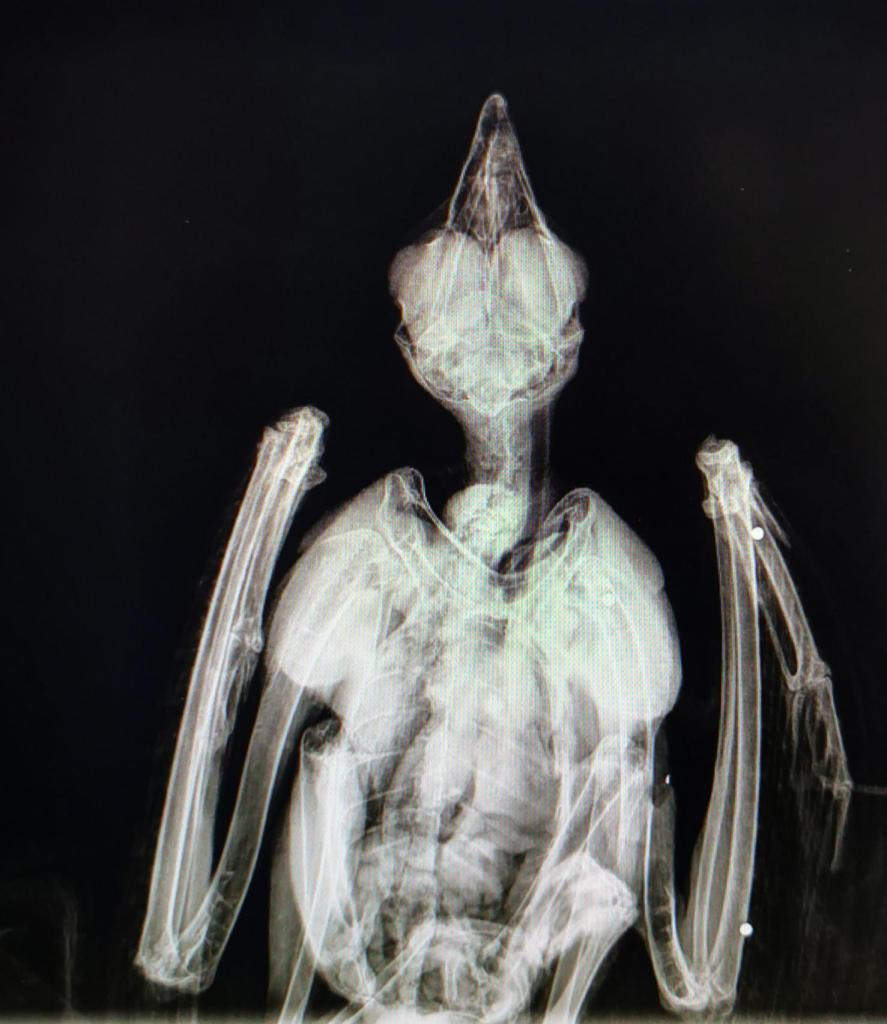

It follows an incident last year when two common buzzards were found dead in Teesdale woodland. Forensic tests indicate they were illegally poisoned with a banned pesticide.

[Two poisoned buzzards. Photo by RSPB]